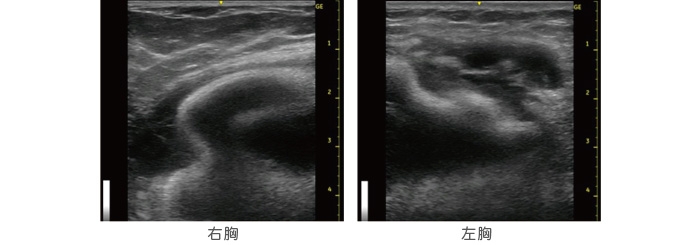

以前こちらの診療録でも「豊胸手術後に左右差が出るのは異常の証」と触れましたが、今回のゲストは、まさにその実例でした。一見すると、大きく腫れ上がった左胸のみに注目してしまいますが、右胸にも触診で明らかな硬さがみられ、破損が疑われました。当院ではカウンセリング時に、無料で最新鋭の機器による超音波検査を提供しています。この方のエコーを確認すると、やはり両胸ともに破損。右胸は豊胸シリコンバッグを包む被膜の中にスペースができてしまっています。さらに左胸は、被膜の中に一瞬腫瘍のようにみえる異常があり、被膜の外にまで液体のようなものが漏れ出していました。エコーを詳細まで確認したところ、その異常も豊胸シリコンバッグの破損による影響であることが分かりました。